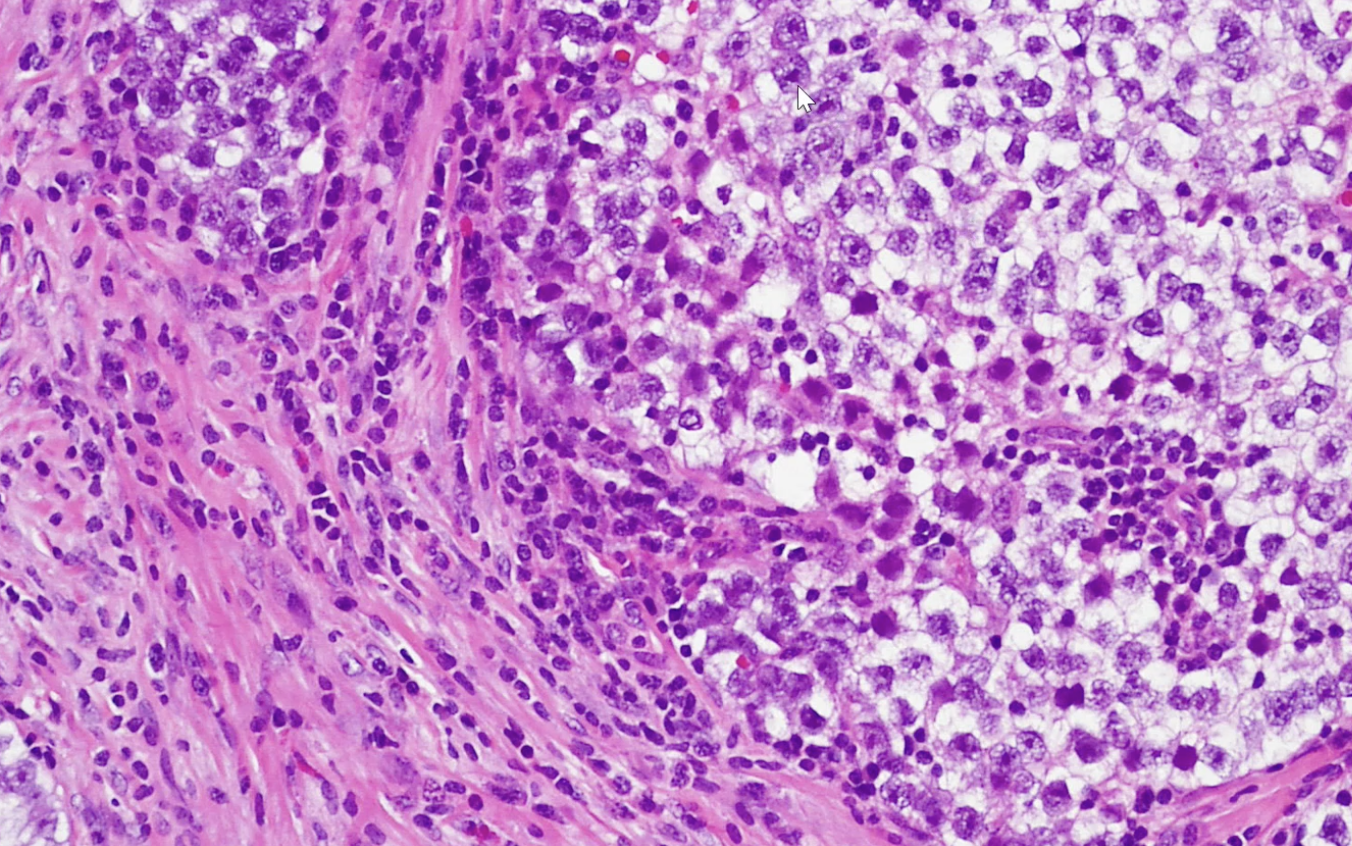

Seminoma

PLAP stain Seminoma